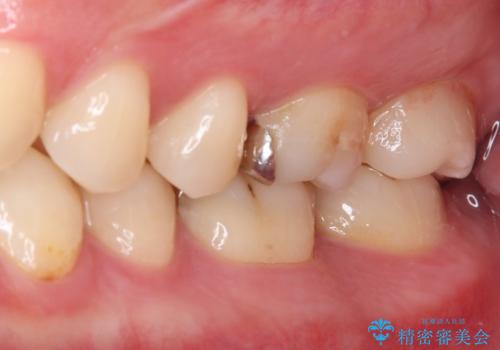

- 数年前他院にて治療した銀歯をやり替え希望の患者様です。

拡大鏡下で、銀歯、むし歯の除去を行い、セラミックインレーに適した形に整えました。